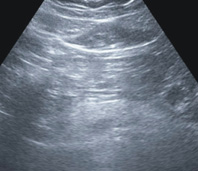

脂肪胰臟與新陳代謝疾病也是很有關係,脂肪胰可能為代謝症候群警訊,一般以腹部超音波先行診斷(如:圖二)。如果有三高(高血壓、高血糖、高血脂)則按照上述飲食建議。脂肪胰臟的人建議少油少糖;例如:肥肉、油炸食物(天婦羅、炸雞排)、加工肉品(香腸、火腿、貢丸)、絞肉類食物(水餃、鍋貼、水煎包、小籠包)必須少吃。減少甜食、含糖食物與飲料還有減少酒精攝取。

圖二、脂肪胰臟與新陳代謝疾病,以腹部超音波先行診斷